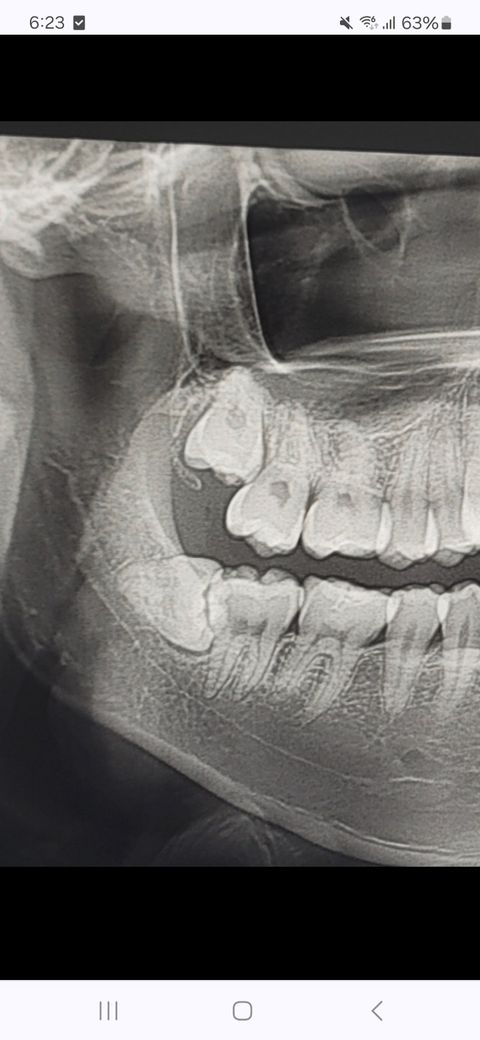

매복 사랑니 발치가 어려운가요? 사진O

안녕하세요 아랫쪽 사랑니가 몇년간 괜찮다가 요새 쿡쿡 쑤셔서 발치를 하려고 하는데 신경에 가까워서 대학병원에서 발치하는걸 추천하시더라구요

많이 까다로운지, 위에 사랑니는 겉으로 드러나지 않았는데 발치하는게 좋은지 궁금합니다

사랑니의 위치가 신경과 가까운 편이기 때문에 대학병원에서 발치를 하시는 것이 좋겠습니다.

사진 상으로 보아서도 신경과 가까울 가능성이 커 보입니다. 따라서 안전하게 발치하기 위해서는 대학병원도 권할 수 있고 구강악안면외과 전문의 선생님이 있는 병원에서 발치가 가능할 수도 있겠습니다. 물론 제일 안전한 것은 대학병원입니다.

• 사랑니가 기울어져 나 있지만 뿌리가 모아져 있기 때문에 나오는데 크게 불편감은 없을 것으로 생각됩니다 사랑해를 뽑을 때는 사랑니를 잘라서 뽑게 되는데 상대적으로 어려운 술식이기 때문에 숙련된 전문가에게 발전하는 것이 좋을 수 있습니다

• 안녕하세요 치과의사 김철진입니다. 상악은 크게 난이도가 잇어 보이진 않지만, 하악 발치는 신경관과 가까워서 난이도가 잇습니다.

• 아래쪽 매복 사랑니의 경우 앞의 어금니와 근접하게 맞닿아 있어 발치 난이도가 높은 치아입니다. 방치시에는 앞의 어금니 뿌리까지 손상시켜 나중에는 두개의 치아 모두 발치가 필요로 됩니다. 따라서 가능한 빠른 시일내에 발치를 권하며, 매복 사랑니 경험이 풍부한 구강외과 전문의에게 치료를 받길 권합니다.

• 위,아래 둘다 어느정도 난이도가 있습니다 위의 경우 상악동 천공에 유의해야하고 아래는 신경손상유의해야 합니다 꼭 대학병원까진 가지 않더라도 ct가 있는 치과를 가는것을 추천합니다